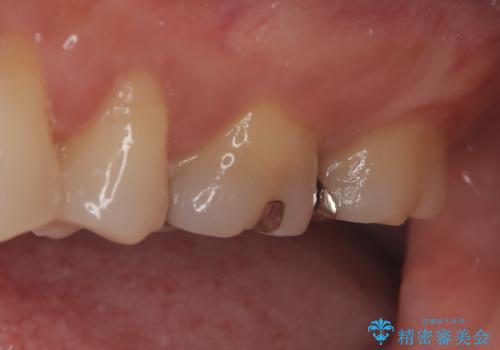

【メタルフリー】セラミックインレーの修復

- メタルフリーを希望された患者さんです。

金属を除去し虫歯の処置をしたあとセラミックインレーにて修復しました。

- 14万円費用は治療当時の料金となります